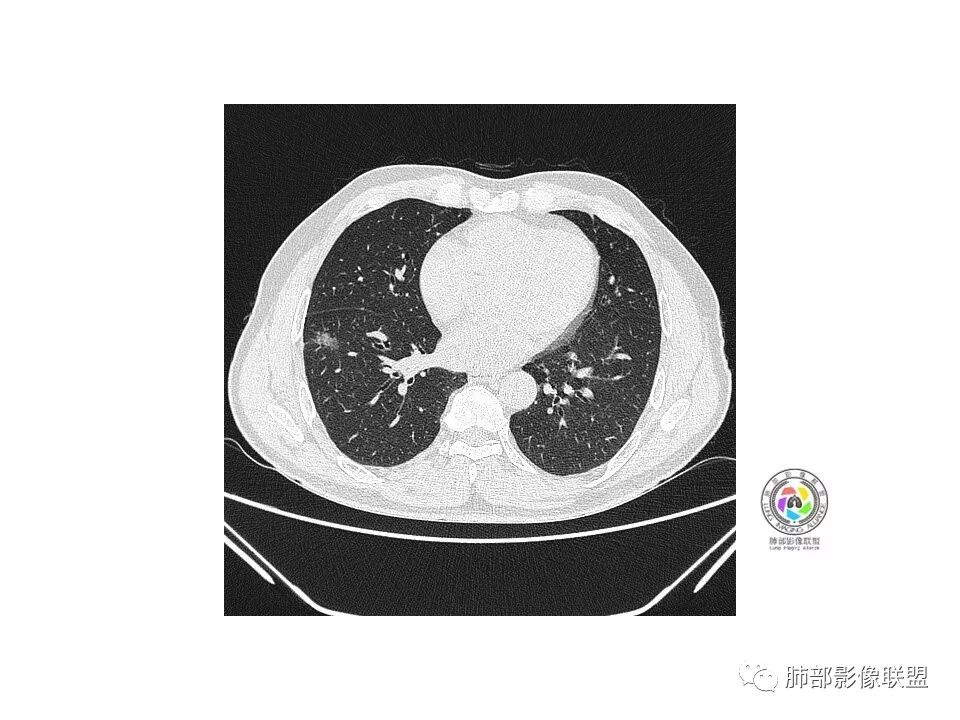

右肺下叶见边界清晰混合磨玻璃密度影,目测内见实性结节小于5mm,有浅分叶,前缘小叶间隔阻挡,月牙铲?胸膜牵拉,老年患者,MIA可能,鉴别炎性病变,抗炎后复查

患者老年男性,以咳嗽 、咳痰3天就诊,胸CT:右肺下叶前基底段mGGO,内可见血管形态改变,细支气管扩张,病灶边界清,边缘可见月牙铲。考虑恶性,腺癌?但建议先抗炎治疗后复查

老年男性、咳嗽咳痰三天,右下前基底段GGN,血管影增多,伴类似的树芽,边缘稍模糊,考虑结核。

右肺下叶磨玻璃结节,密度不均,边缘收缩,胸膜牵拉,考虑炎性,建议复查,除外腺癌。

右肺下叶混合磨玻璃结节,边缘清晰,浅分叶,月牙铲,胸膜牵拉,血管进入,考虑MIA可能,鉴别炎性病变

磨玻璃结节,边缘清楚,浅分叶,月牙铲,考虑腺癌可能,抗炎后复查。

右肺下叶混合磨玻璃密度结节影,局部胸膜牵拉,月牙铲,考虑腺癌

磨玻璃小结节,有明显收缩性表现,胸膜凹陷,考虑腺癌

患者老年男性,咳嗽  咳痰3天就诊。胸部CT:右肺下叶前基底段混合磨玻璃结节,边缘清楚,可见毛刺、胸膜牵拉、血管集束、月牙铲征象。综合考虑微浸润腺癌可能大。

右肺下叶前基底段混合磨玻璃结节,边界清,浅分叶,胸膜牵拉,月牙铲,血管进入,考虑:微浸润腺癌可能性大,抗炎后复查。

老年男性,右下叶孤立ggo,先抗炎2-3周复查,无变化→切,小了→炎性

40岁以上男性,孤立混合磨玻璃,边界清楚,分叶,胸膜凹陷,血管集束、穿行,考虑腺癌。

右肺下叶孤立混合磨玻璃结节,隐约细小毛刺,似有月牙铲,胸膜稍牵拉,考虑MIA(微浸润腺癌)可能,常规飞一下。